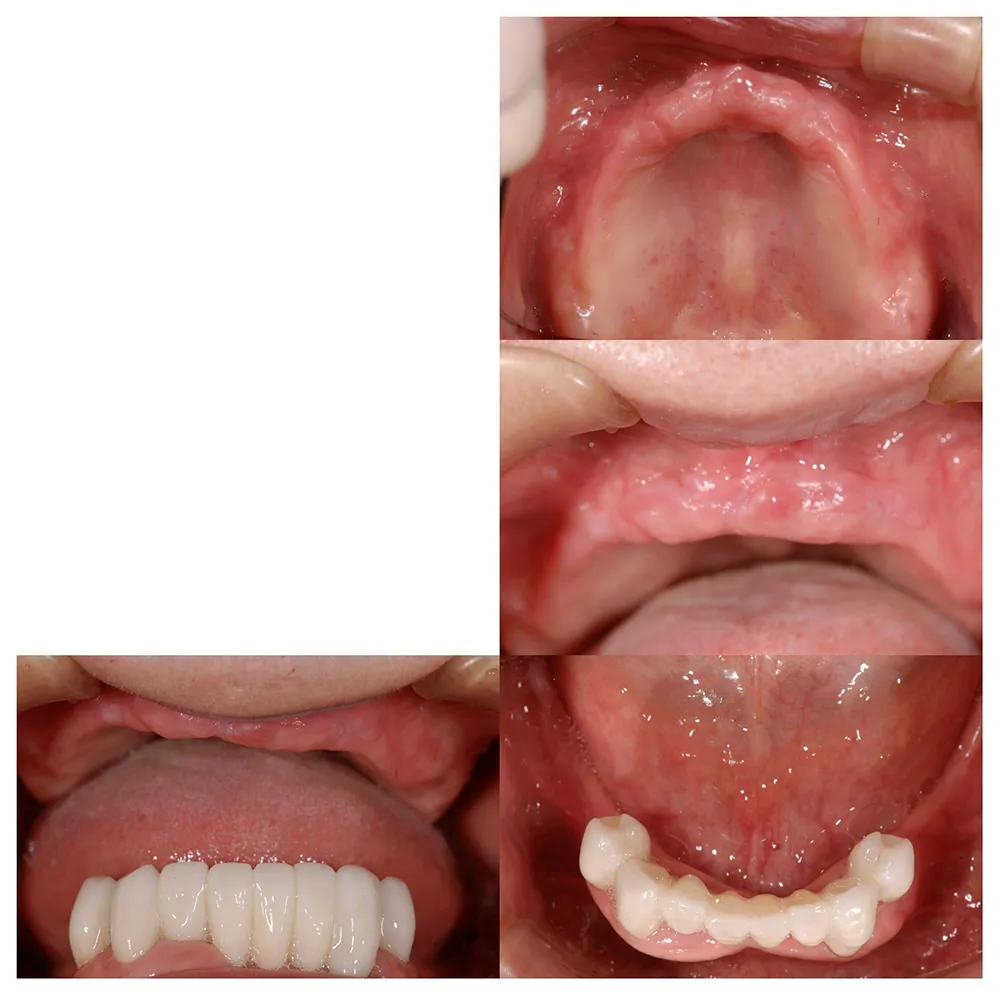

■治療前:上下顎 義歯での食事に満足されていない

■治療後:上下顎 複数本のインプラントを使い固定式で治療

| 主訴 | 現在義歯を使用しているが、しっかりと咬んでなんでもおいしく食事したい |

| 治療方法 | 上下顎 複数本のインプラントを使用しての治療 |

| 治療期間 | 約1年 |

| 通院回数等 | 約20回 |

| 費用 | 約600万円(税込) |

| リスク・副作用 | 術後の腫れ・痛み |

上下に入れ歯を入れていましたが、ここ数年しっかりと噛む事がなかった患者様です。何でもおいしく食事ができるようになりたいと希望され、来院されました。

治療法としては、最小限のインプラントの本数で対応ができるように、オールオンフォーを意識した治療法で対応させて頂きました。

| 主訴 | 噛めない |

| 治療方法 | 上顎8本、下顎6本のインプラントを埋入し固定性の入れ歯で治療した |

| 通院回数等 | 20回 |

| 費用 | 上顎4,130,000円 下顎3,630,000円(税込) |

| リスク・副作用 | 治療後に一時的に腫れることがある |